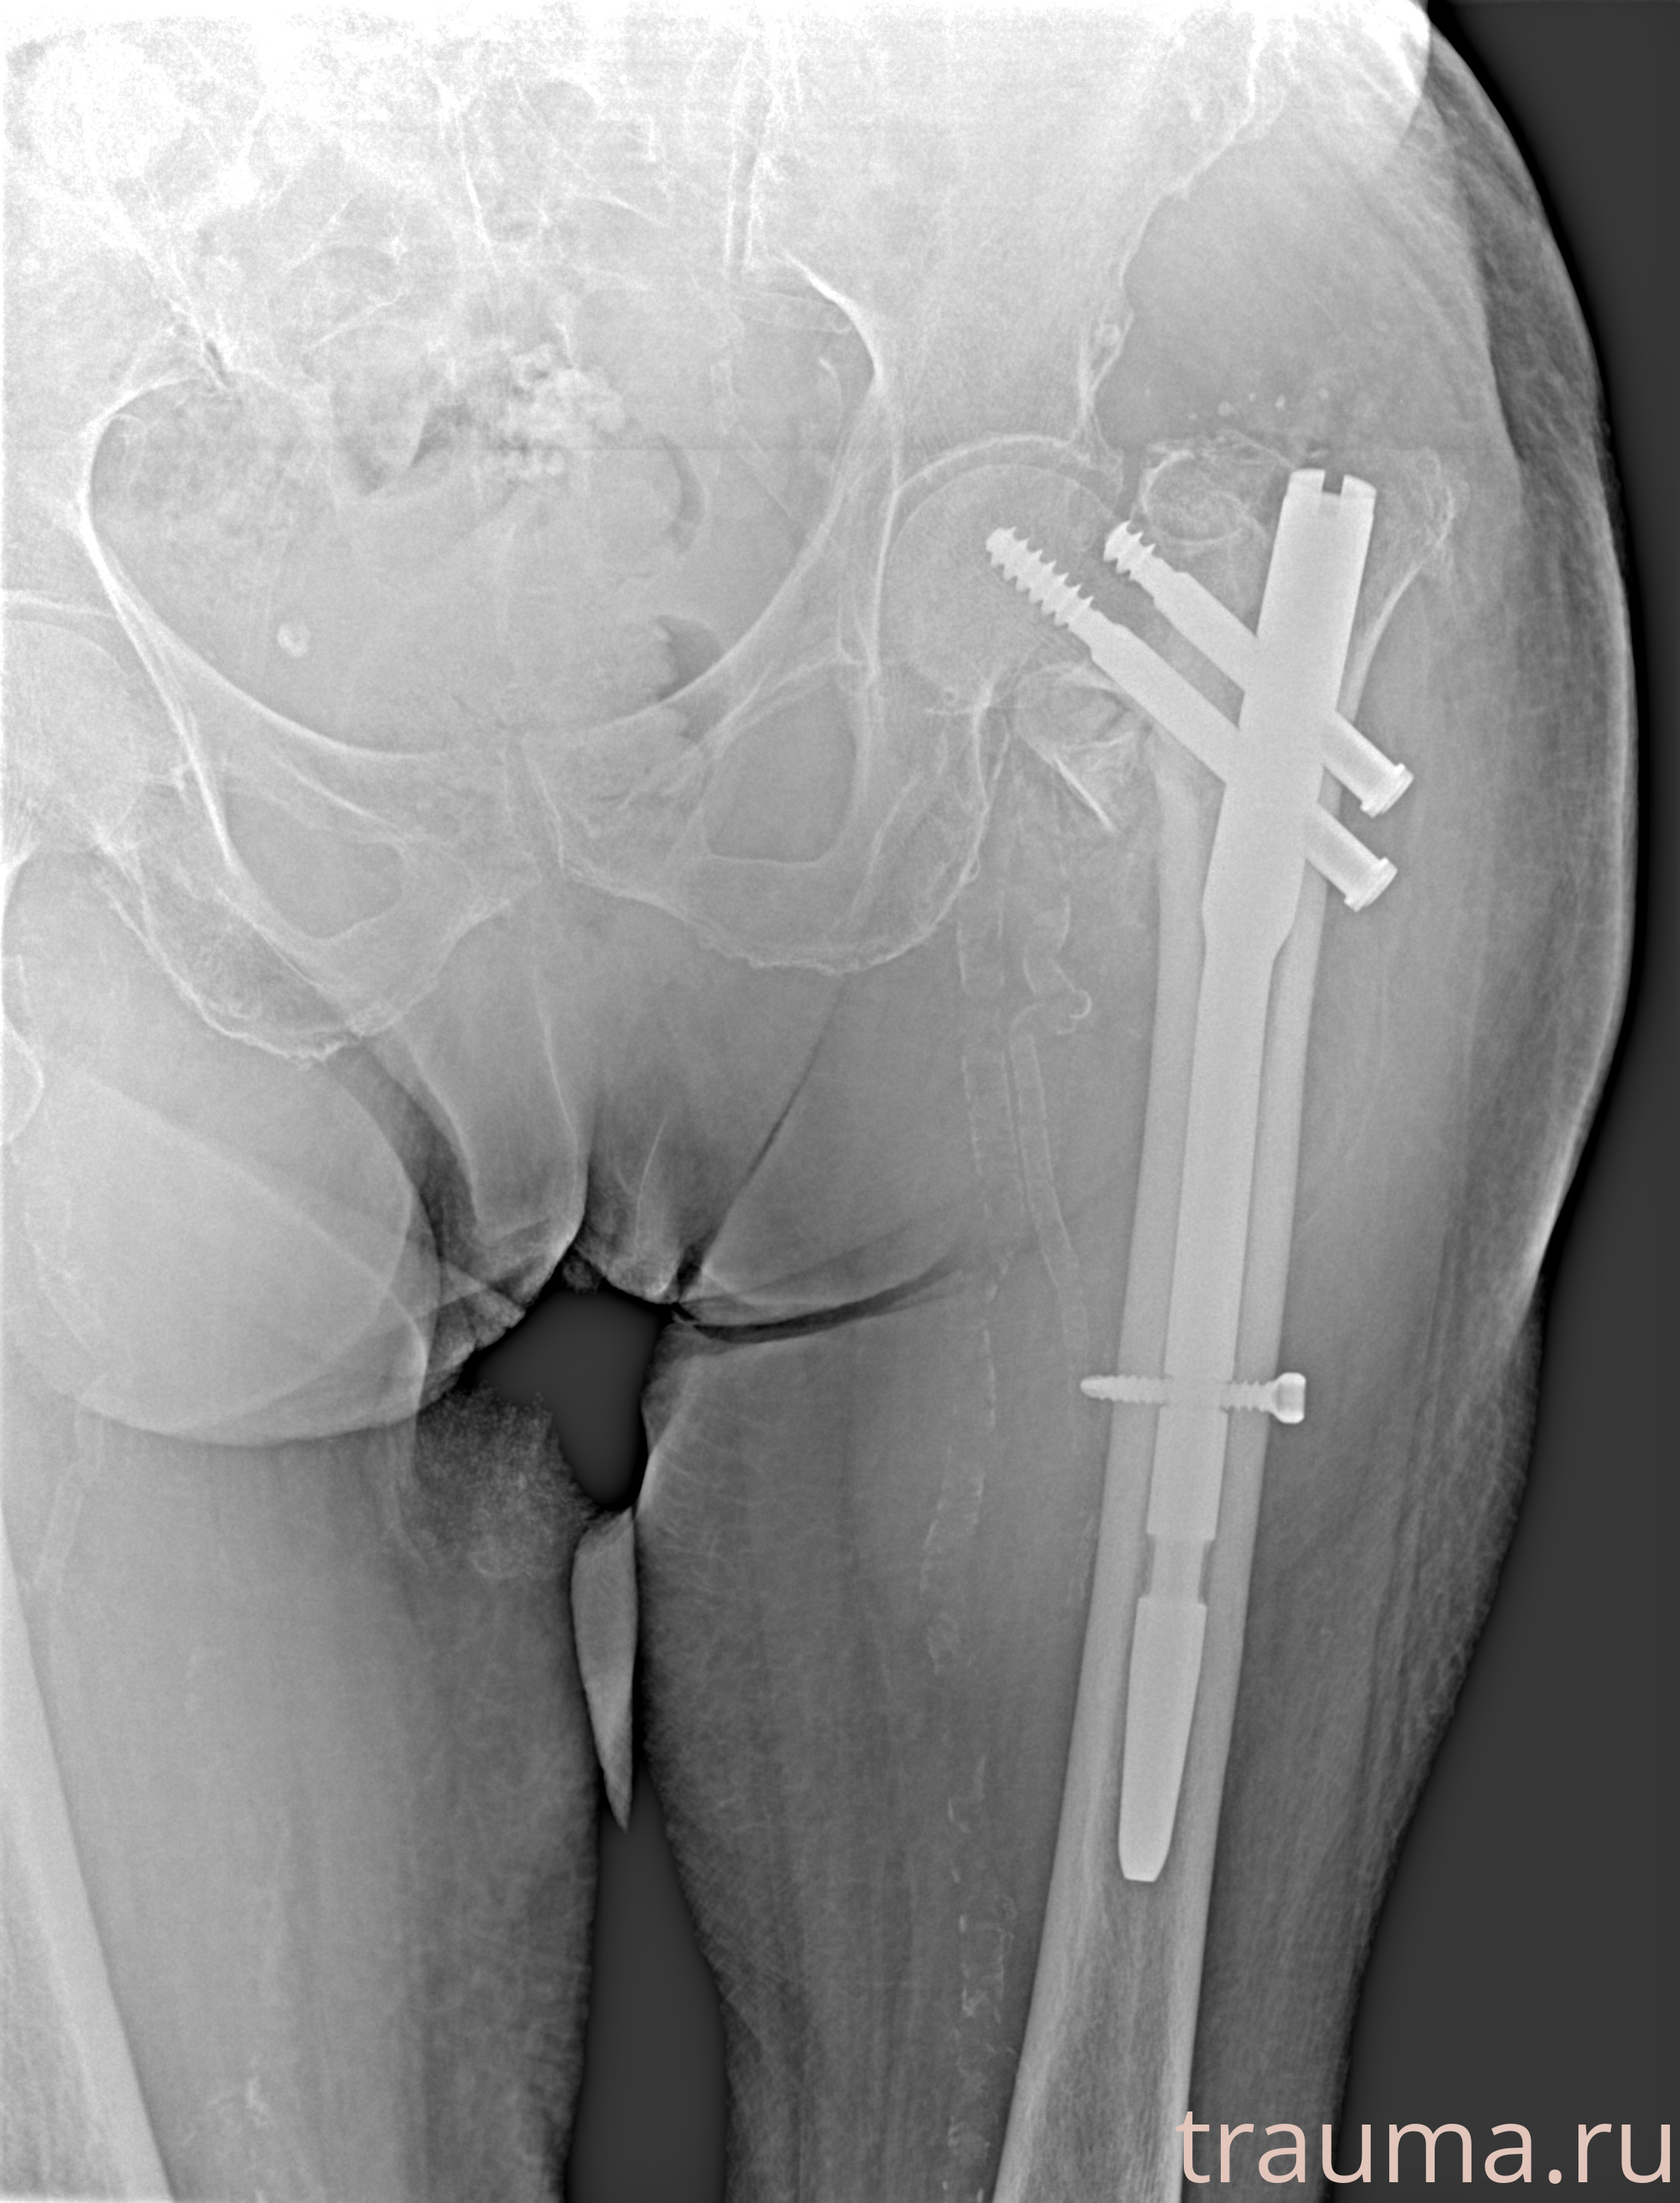

Рентгенограммы

Рентген на дому: по вашему адресу приезжает врач-рентгенолог, травматолог-ортопед с мобильным рентгеновским аппаратом, проводит диагностику травмы или заболевания, делает необходимые рентгенограммы, дает рекомендации по дальнейшему лечению. Получить качественные снимки в домашних условиях возможно благодаря уникальной методике, разработанной МосРентген Центром для института  Склифосовского